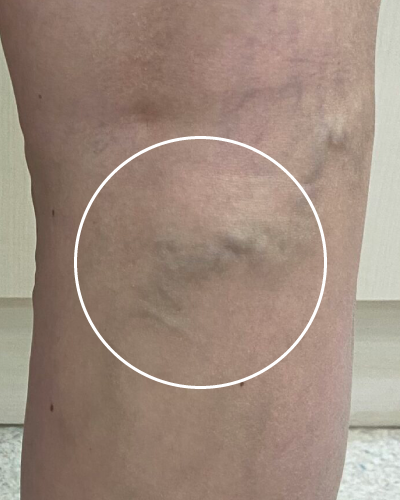

하지정맥류 진단의 키포인트,

'혈액의 역류'

혈관이 튀어나오지 않았어도 초음파 검사상 혈액의 역류가 진행 중이면, 이 역시 ‘잠복성 하지정맥류’로 진단합니다.

한 번 발병하면 시간차를 두고 증상이 점점 심해지므로, 근본 원인을 찾아 제때 치료하는 것이 매우 중요합니다.

혈관은 튀어나오지 않았으나 혈액 역류가 확인됨

(23.07.11 사진)